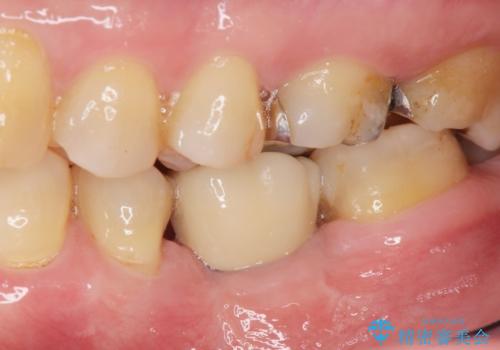

インプラントによる咬合機能回復

- 歯を破折により失い、インプラント治療を希望され来院されました。

インプラントを埋入し咬合機能を回復するとともに周囲の骨造成も同時に行っていきます。

インプラントを適切な位置に埋入することで、清掃性が高くしっかりと咬合力に耐えられるようなインプラント治療を行うことができます。